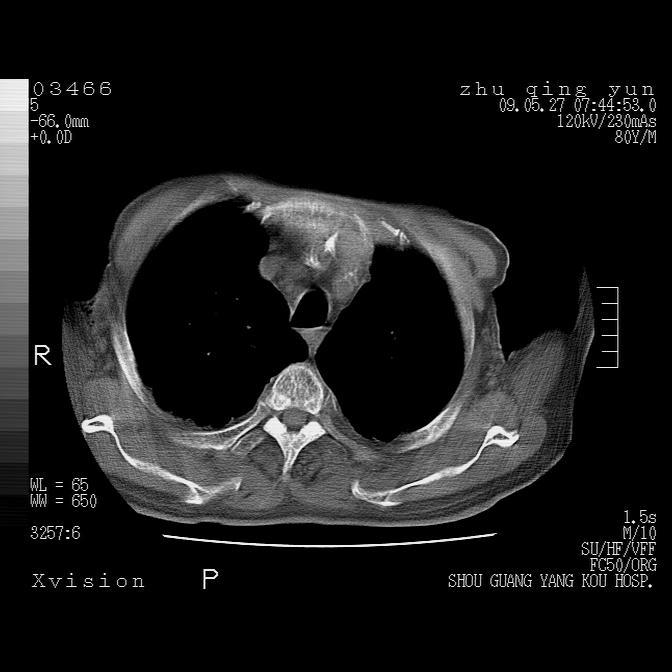

病人男性,年龄80,气喘来院,其他病史不太详细,1月前有过恶心,呕吐,在当地人民医院做过钡餐,诊断胃炎,

1)考虑左肺中央型肺癌并阻塞性肺炎,后下纵隔受侵伴纵隔淋巴结转移。2)双侧少量胸腔积液,胸膜增厚。3)心包积液。

左肺下叶见多发片状及结节状病灶,左肺基底段支气管闭塞,纵隔内见多发淋巴结肿大,纵隔向左侧移位,左侧胸廓变小。应该是左肺下叶中心型肺癌,纵隔淋巴结转移,左侧肺内转移,左肺基底段肺不张,阻塞性肺炎。

1)考虑左肺中央型肺癌并左肺下叶阻塞性肺炎、不张;左胸膜腔积液、心包积液、纵隔淋巴结转移;癌肿累及左心房。2)左心室大。冠状动脉壁钙化斑。

1)考虑左肺中央型肺癌并左肺下叶阻塞性肺炎、不张;左胸膜腔积液、心包积液、纵隔淋巴结转移;癌肿累及左心房。